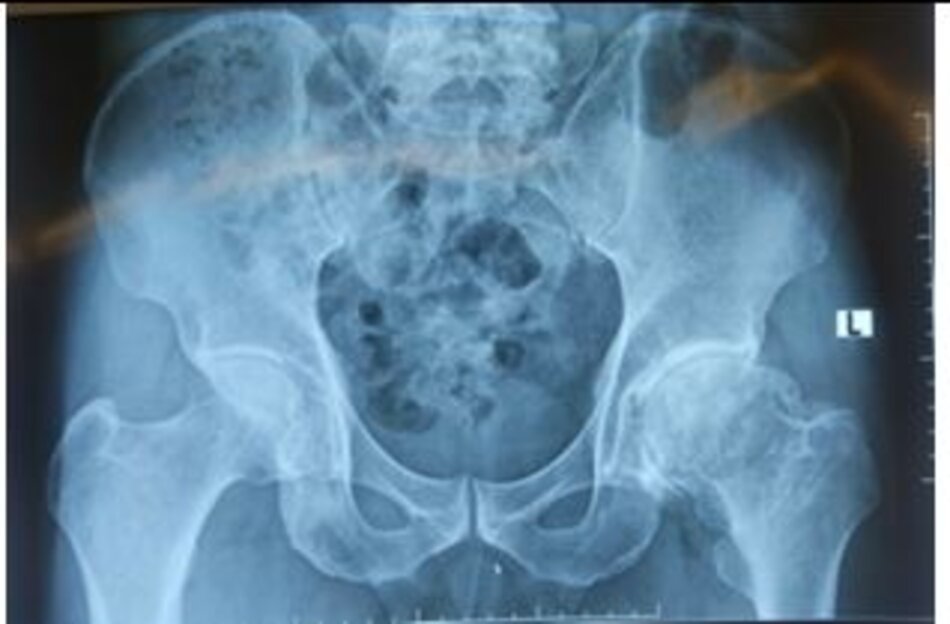

Hình ảnh vỡ xương chậu phức tạp

Hình ảnh đường mổ và phim chụp sau mổ đạt kết quả đúng giải phẫu